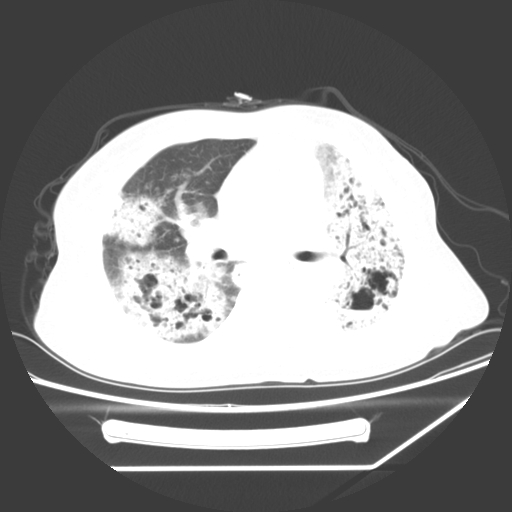

标题: CT25393:病人45岁,咳嗽,吐黄痰带血丝,发热,胸闷月余 [打印本页]

1、左肺中央型肺癌并双肺弥漫性转移   2、双肺部感染    3、肺大泡     4、左侧胸腔积液

双侧肺弥漫性病变,可见“空泡征”及“蜂窝征”,考虑肺泡癌可能性大,左侧胸腔积液,考虑胸膜受累可能!

考虑肺泡癌,建议排除感染。

考虑肺泡癌

1)不排除肺泡癌可能。2)左侧胸腔积液。